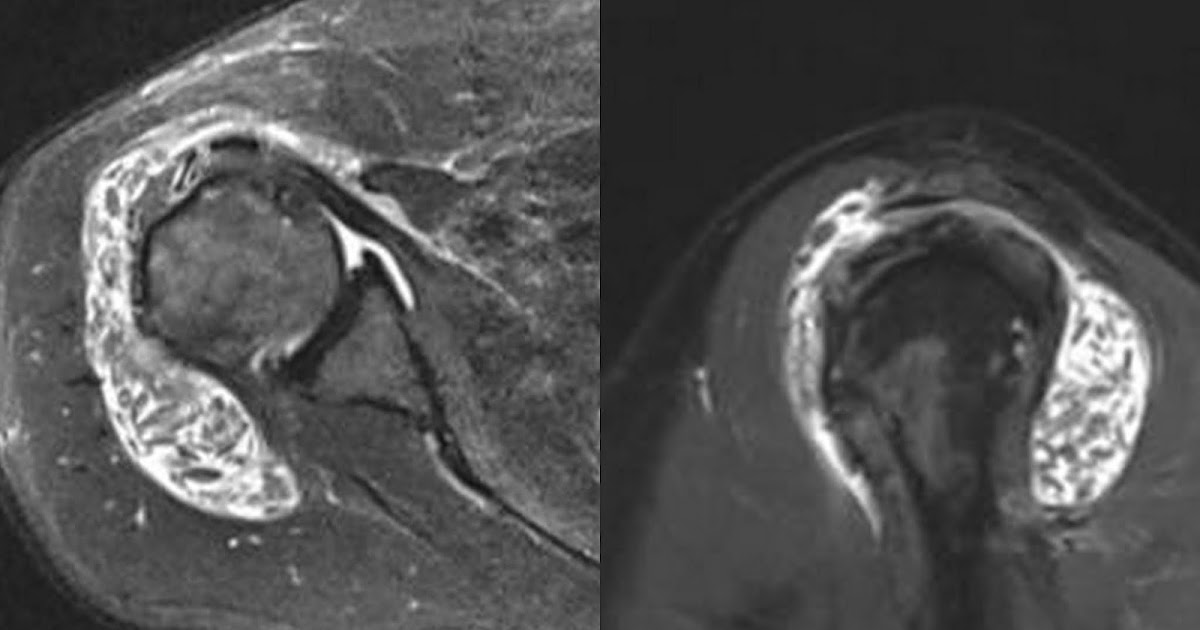

Figure 2 from Severe SubAcromial Bursitis with Rice Bodies in a

Figure 1 from Imaging features of shoulder tuberculosis with rice What Is A Rice Body They are located in the synovial fluid,. the meaning of rice body is any of the smooth glistening ovoid particles resembling grains of rice that occur in joints and the. the video reviews the pathogenesis, diagnosis, and management of rice bodies in the articular space of the shoulder and discusses the case. What Is A Rice Body.

Figure 2 from Subacromial bursitis with rice bodies as the presenting What Is A Rice Body They are located in the synovial fluid,. the video reviews the pathogenesis, diagnosis, and management of rice bodies in the articular space of the shoulder and discusses the case. the meaning of rice body is any of the smooth glistening ovoid particles resembling grains of rice that occur in joints and the. What Is A Rice Body.

Figure 2 from Severe SubAcromial Bursitis with Rice Bodies in a What Is A Rice Body the meaning of rice body is any of the smooth glistening ovoid particles resembling grains of rice that occur in joints and the. They are located in the synovial fluid,. the video reviews the pathogenesis, diagnosis, and management of rice bodies in the articular space of the shoulder and discusses the case. What Is A Rice Body.